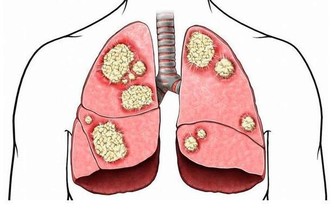

導致乙醛在體內蓄積,損害肝臟功能,增加肝病風險,長期飲酒也會導致食道癌的發生。

美國《PlosMedicine》雜誌刊載了一篇名為《酒精性臉紅的反應:來自於飲酒關於食管癌未知的風險因素》的論文,美國國家酗酒與酒精中毒研究所和日本久里濱酒精過敏研究中心的研究人員的聯合研究發現,對於體內缺乏乙醛脫氫酶2或這種酶不能正常發揮作用的人群來說,患食道癌的風險隨酒精攝入量的增多而增大。

5. 蘆筍:富含葉酸,能預防癌細胞擴散,促使細胞生長正常化,能有效改善肝功能異常症狀。

對高血壓、血管硬化、心髒病、糖尿病、膀胱炎、急慢性肝炎及肝硬化有一定的輔助治療效果。